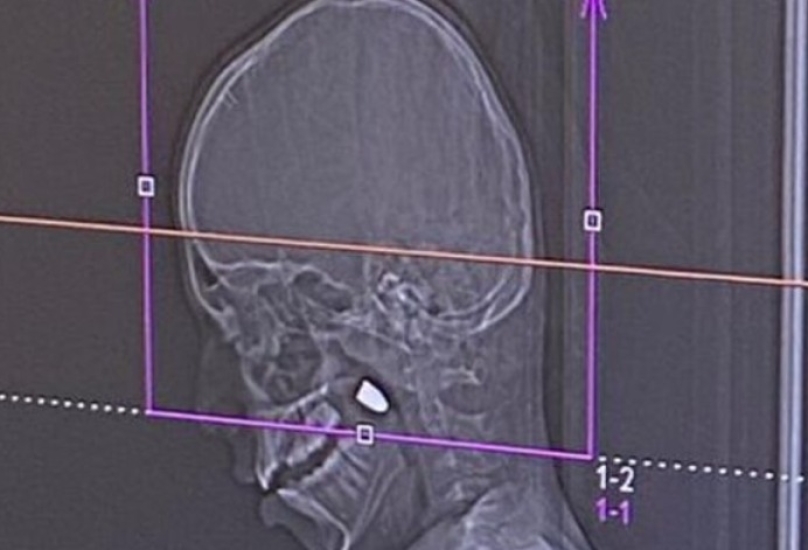

حيفا | نجحت الطواقم الطبية في المركز الطبي رمبام أمس، في إجراء عملية جراحية دقيقة ومعقدة لاستخراج رصاصة استقرت في رأس طفل يبلغ من العمر 11 عاماً من قرية المغار، كان قد أصيب بعيار ناري طائش خلال احتفالات ليلة رأس السنة الميلادية.

بدأت الواقعة حين صعد الطفل إلى سطح منزله لمشاهدة احتفالات العام الجديد، ليعود لعائلته مصاباً بنزيف في الوجه. وبعد فحوصات أولية في مستشفى "بوريا" كشف التصوير الطبقي ($CT$) عن وجود رصاصة مستقرة خلف الفك، تم نقله على الفور إلى مستشفى رمبام في حيفا نظراً لخطورة الحالة وحاجتها لتخصصات دقيقة.

تصريح طبي: أوضح الدكتور صالح نصير، الأخصائي في قسم جراحة الفم والفكين في رمبام، أن الرصاصة اخترقت عظام الجمجمة واستقرت في منطقة حساسة بالوجه، مؤكداً أن نجاح العملية دون مضاعفات عصبية يُعد "معجزة طبية"، حيث كان من الممكن أن تؤدي الرصاصة إلى أضرار دماغية دائمة.